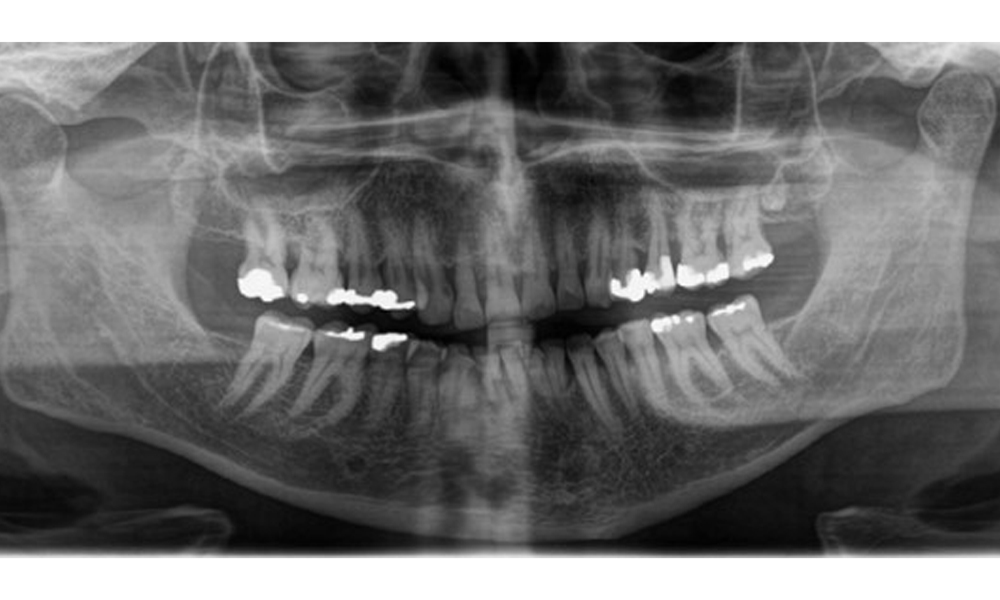

Radiological findings

There is fully dentulous adult dentition with generalized bone loss of between 20-50% and multiple areas of vertical bone loss. Radiological examination revealed no visible caries. (Fig. 7)

Panoramic X-ray image showing generalized radiological bone loss with multiple vertical defects of between 20% to 50%.

Fig. 7 Panoramic X-ray image showing generalized radiological bone loss with multiple vertical defects of between 20% to 50%. © Dr R. Krapf